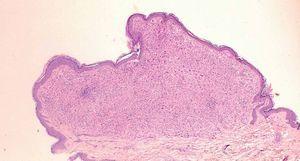

Fig. 3.—Densa reacción inflamatoria linfohistiocitaria bien delimitada que ocupa toda la dermis papilar. (Hematoxilina-eosina, ×40.)

El estudio histológico de las lesiones es característico, con hallazgos similares a los encontrados en la forma juvenil y con una inmunohistoquímica que permite diferenciarlo sin problemas de las formas más agresivas de histiocitosis de células de Langerhans (HCL)9,10 . Consiste en la presencia de un infiltrado denso linfohistiocitario bien circunscrito en dermis papilar, que puede ocupar la totalidad de la dermis. En las fases más tempranas se observa un infiltrado histiocítico monomorfo, sin lípidos. En fases más tardías, cuando las lesiones están más evolucionadas, se aprecian en el infiltrado células espumosas, que corresponden a histiocitos cargados de lípidos, junto con células gigantes tipo Touton y tipo reactivas a cuerpo extraño. Acompañando a este infiltrado hay también cantidades variables de linfocitos, eosinófilos y neutrófilos. En las formas más avanzadas puede haber fibrosis. En el estudio inmunohistoquímico, los marcadores de células macrofágicas, CD68 y HAM56 son positivos, así como el marcador de dendrocitos dérmicos FXIIIa, mientras que los marcadores de células de Langerhans S100 y CD1a resultan negativos. En el estudio ultraestructural no se encuentran gránulos de Birbeck en el interior de las células.